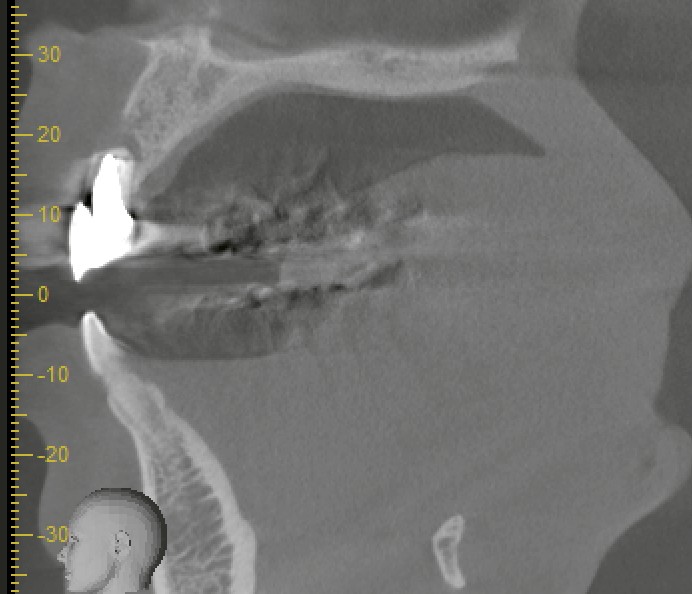

インプラントは確かに優れた治療法ですが、今回のケースでは問題がありました。

抜歯部位の骨欠損が大きく、骨造成(骨を補う手術)が必要だったのです。さらに、両隣の歯肉の高さや審美性を考慮すると、1回の手術だけでは難しく、複数回に分けて治療が必要になる可能性がありました。